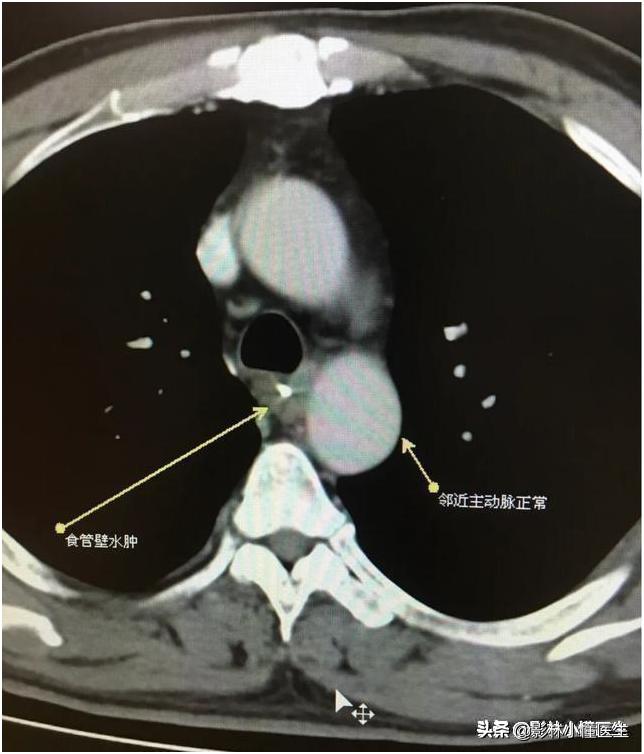

例2

鱼刺刺穿食管及主动脉壁,治疗费用高、预后极差。